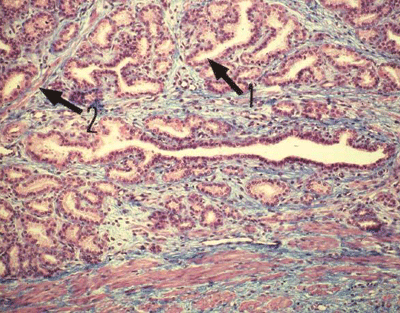

Histologie de la prostate

(Photo : webapps.fundp.ac.be)

1. La substance glandulaire est divisée en lobules et comportent des groupes de glandes composées tubulo-alvéolaires (1).

• La capsule, les parois des lobules et le conjonctif péri-glandulaire sont riches en fibres musculaires lisses (2) qui se contractent au moment de l'.

• Les conduits excréteurs se déversent dans les canalicules prostatiques qui s'ouvrent dans le sinus prostatique de l'urètre.